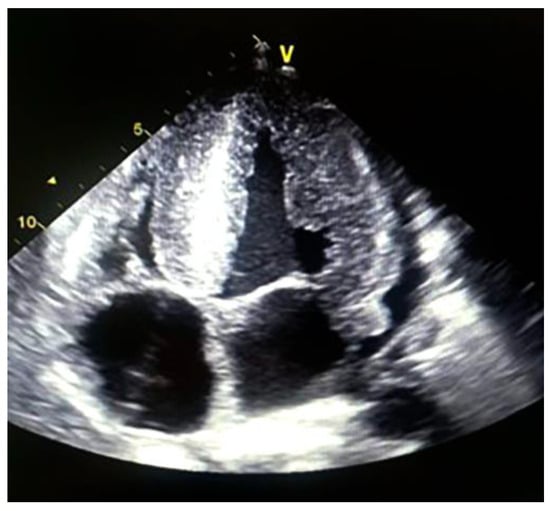

| Myocardiopathy on echocardiogram | Yes | Yes | Yes |